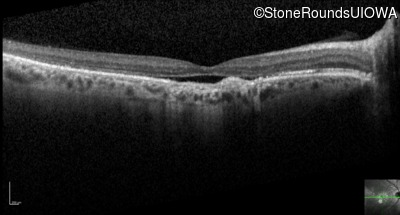

Optical Coherence Tomography - Right - 20/100

Exemplar / OCT Stack